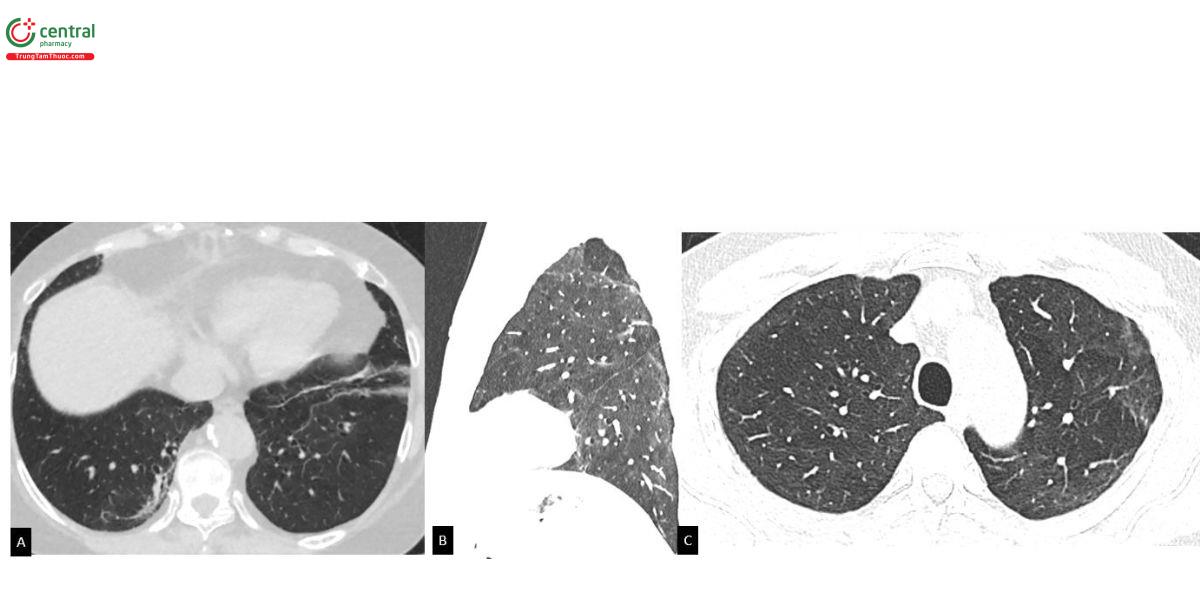

3.5 Phân biệt ILAs và tổn thương tồn lưu sau COVID-19

Nghiên cứu của Lee và cs (2024) trên 40 trường hợp ILAs (20 không xơ hoá, 20 xơ hoá) và 20 trường hợp hậu COVID-19 (theo dõi sau mắc trên 6 tháng) cho thấy bác sỹ Chẩn đoán hình ảnh có khả năng chẩn đoán tốt nhưng độ đồng thuận ở mức trung bình trong phân biệt sẹo tồn lưu hậu COVID-19 và ILAs [25]. Nhầm lẫn dễ xảy ra trong phân biệt sẹo COVID-19 và ILAs không xơ hóa và khi đó, thông tin về tiền căn mắc COVID-19 là đặc biệt quan trọng. Ở những bệnh nhân từng mắc COVID-19 nặng hoặc đã có tổn thương phổi trên CLVT sau COVID-19, ILAs không xơ hóa thường được loại trừ.

Các đặc điểm hình ảnh phân biệt ILAs và sẹo hậu COVID-19 [25] bao gồm: Cách phân bố ưu thế dưới màng phổi, vùng lưng, đáy phổi và các kén khí (không bao gồm khí phế thũng) thường gặp hơn trong ILAs. Tổn thương quanh phân thùy phổi, quanh cây mạch máu phế quản, các dải xơ xẹp, và tưới máu dạng khảm thường gặp hơn trong hậu COVID-19. Tổn thương chiếm hơn 25% thể tích phổi thường gặp hơn trong hậu COVID-19. Kiểu hình kính mờ ưu thế thường gặp trong hậu COVID-19 và ILAs không xơ hoá hơn các trường hợp ILAs xơ hoá.